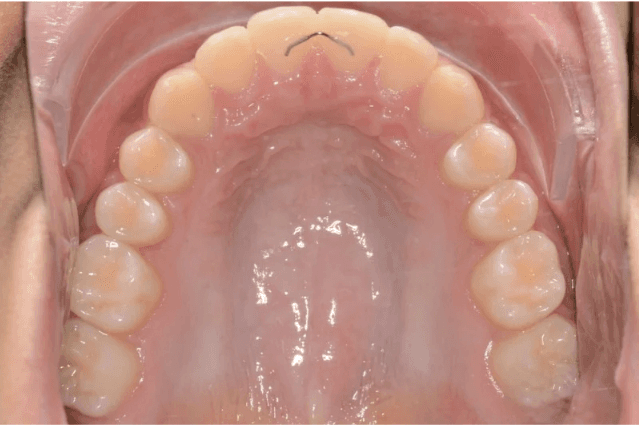

Final results

INTRAORAL